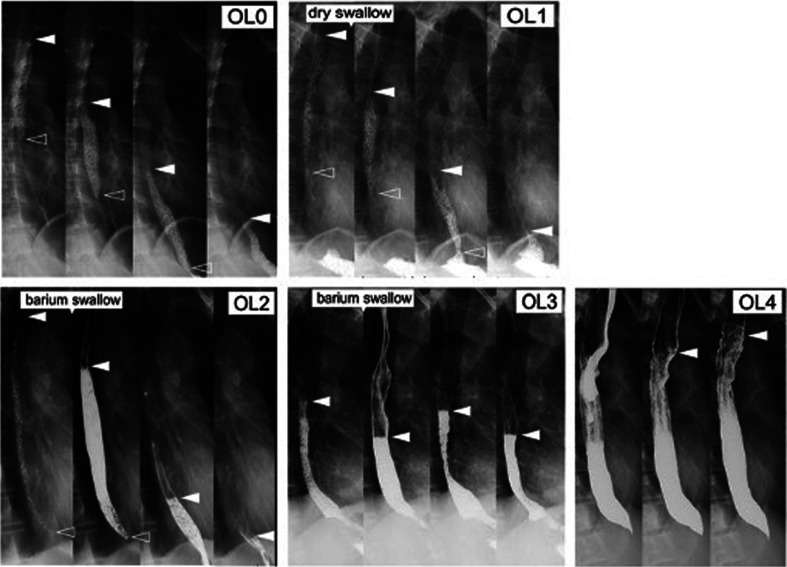

A number of factors have been recently associated with the development of disorders of gut-brain interaction (DGBI), including genetic predisposition, early-life environment, intestinal microbiota, infection, microinflammation, and increased mucosal permeability. In addition, impaired gastrointestinal motility is important not only as a cause of DGBI but also as a consequent final phenotype. Gastrointestinal motor measurements are the predominant method for the assessment of and therapeutic intervention into motor abnormalities. As such, these measurements should be considered for DGBI patients who do not respond to first-line approaches such as behavioral therapy, dietary modifications, and pharmacotherapy. This comprehensive review focuses on the functional changes in the upper gastrointestinal tract caused by DGBI and describes ongoing attempts to develop imaging modalities to assess these dysfunctions in the esophageal and gastric regions. Recent advances in imaging techniques could help elucidate the pathophysiology of DGBI, with exciting potential for research and clinical practice.